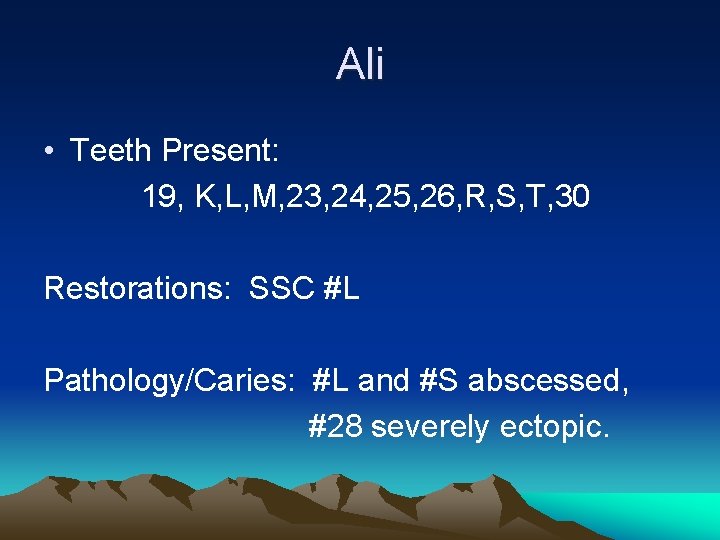

Ali • Teeth Present: 19, K, L, M, 23, 24, 25, 26, R, S, T, 30 Restorations: SSC #L Pathology/Caries: #L and #S abscessed, #28 severely ectopic.

Ali A Moyer’s space analysis predicted there to be 2. 3 mm of excess space in the mandible. Make a treatment plan and appointment sequence for the mandibular arch only.

Ali Tx Plan • Extract #L, S and T and Place LLHA • #L and S due to abscess • #T due to ectopic #28 – Appt #1: Fit bands and Impress for LLHA Extract #L – Appt. #2: Seat LLHA Extract #S, T

Ali • Assuming normal dental development, at what age will the space maintainer you placed no longer be needed? • Answer: When #21, 28 and 29 erupt. • Around age 12 years